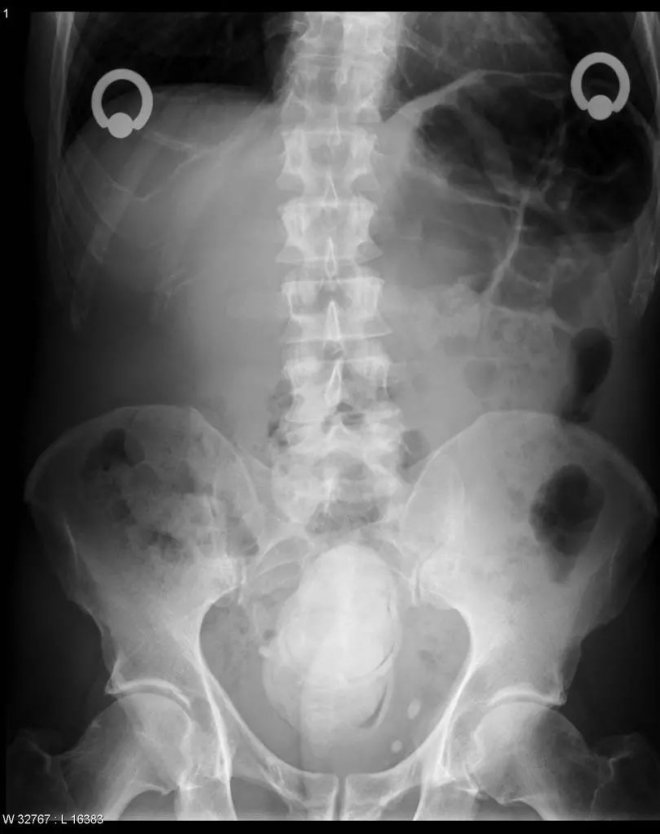

橙子

下腹部中央有一個圓形的異物,原來是患者自己塞進去的橙子。水果雖然是好東西,但不是這樣用法